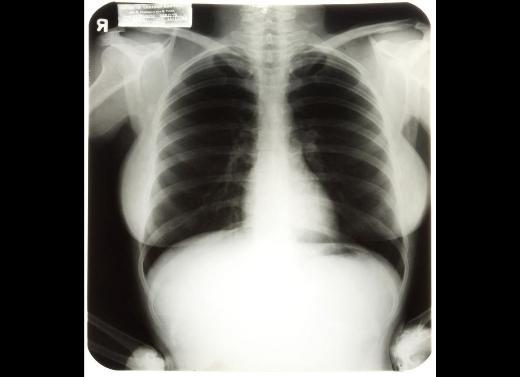

15. Bu görüntünün özelliği ise sahibinden geliyor. Marilyn Monroe'nun 1954'teki bir hastane ziyareti sırasında çekilen üç röntgeni üst üste getirilmişti.

Bu görüntünün özelliği ise sahibinden geliyor. Marilyn Monroe'nun 1954'teki bir hastane ziyareti sırasında çekilen üç röntgeni üst üste getirilmişti.